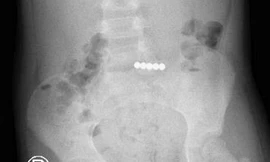

TPO - Nhập viện trong tình trạng đau bụng, nôn ói, bí đại tiện, bệnh nhi được bác sĩ kiểm tra hình ảnh thì phát hiện trong đường tiêu hóa có nhiều dị vật cản quang. Các bác sĩ đã tiến hành phẫu thuật lấy ra 20 viên nam châm và cắt bỏ đoạn ruột bị hoại tử.

TPO - Nhập viện trong tình trạng đau bụng quằn quại, bệnh nhi được bác sĩ kiểm tra phát hiện trong đường tiêu hóa có nhiều dị vật xếp thành hình vòng tròn. Trong quá trình phẫu thuật lấy dị vật, bác sĩ phát hiện 14 viên nam châm hít vào nhau đã khiến bệnh nhi bị thủng ruột.

TPO - Được bạn cùng lớp cho 5 viên bi nam châm nhưng sợ bị cô phát hiện, tịch thu, bé gái 6 tuổi ngậm vào miệng để giấu. Tuy nhiên, trong lúc sơ ý, cháu đã nuốt cả 5 viên bi vào dạ dày và phải nhập viện cấp cứu.

TPO - Trẻ ngậm trong miệng rồi nuốt lúc nào không biết, đến khi đau đớn quằn quại phải nhập viện thì đã bị thủng ruột bởi 2 viên bi nam châm gây ra. Bác sĩ cảnh báo, nuốt dị vật là tai nạn rất nguy hiểm có thể cướp đi sinh mạng của bệnh nhi.

TPO - Nhân dịp sinh nhật, bé gái được mẹ mua cho một bộ đồ chơi có nhiều viên bi nam châm. Trong lúc chơi đùa, bé đã vô tình nuốt phải 4 viên bi khiến ruột bị tắc, nguy kịch đến tính mạng.